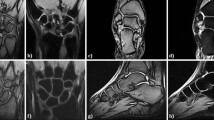

Seventy-two OA patients with informed consent were recruited from the Rheumatology and Immunology Department, Shenzhen People’s Hospital. Each patient diagnosed as OA in line with the classification developed by the Osteoarthritis Criteria Subcommittee of the American Rheumatism Association38. According to X- ray or MRI diagnosis and clinical parameters, Patients with OA can be distinguished erosive inflammatory OA from primary generalized OA7. Patients with other rheumatic diseases, infections or malignant tumors were excluded from the study. Clinical data from each OA patient were recorded, visual analogue scale (VAS) was used to measure pain intensity, with lower scores(0~10) indicating lower levels of clinical symptoms or pain39. Other clinical data containing C-reactive protein (CRP), erythrocyte sedimentation rate (ESR), albumin (ALB), urea nitrogen (BUN) Cr (Creatinine), anti-CENPB antibody and anti-SSA60 antibody were performed. Forty age and sex matched healthy volunteers were recruited from the same hospital as controls (HCs). Demographic and clinical information were listed in Table 1.